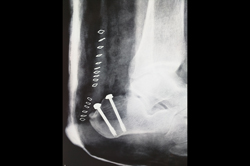

Ankle